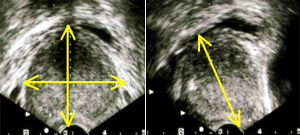

また前立腺のおおよその大きさ・形状と合わせて残尿をみるにはエコー検査が極めて有用です。尿を十分に溜めた状態で恥骨上にプローベを当てれば(高度の肥満症例でない限り)、前立腺の形状を概ね理解することができますし、時には膀胱内病変(腫瘍や結石)の診断にも有用です。また排尿後には残尿も測定可能でありこれにより大まかな排尿状態の理解が可能となります。前立腺体積、残容量ともに3方向を計測し0.55を乗ずることで回転楕円体に近似した体積が測定できます。薬剤治療にもかかわらず症状の改善されない方、あるいは前立腺体積が30ml以上、残尿が50ml以上が続くような場合は一度は泌尿器科の診察を受けられるのがよいかと存じます。体積の測定は3方向を測定し a x b x c x 0.55cm3 で計算する。(図の残尿であれば6.5 x 4.5 x 3.5 x 0.55=65.3ml)

前立腺の形状の理解と体積測定